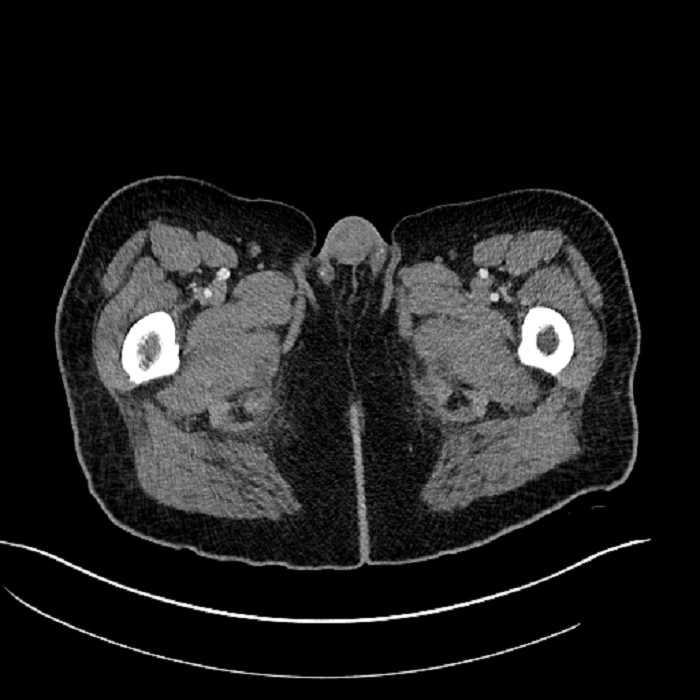

• High grade stenosis of the left common iliac artery, with the left internal and external iliac arteries remaining patent

High grade stenosis of the left common iliac artery. The left external and internal iliac arteries are patent.

Hepatic abscess showing the double target sign with low density internally surrounded by a thin inner enhancing rim (red arrow) and ill-defined outer low density rim (yellow arrow). Blue arrow indicates an internal septation. Red arrows: additional smaller subcapsular abscesses. Red arrow: focal contained perforation associated with diverticulitis.